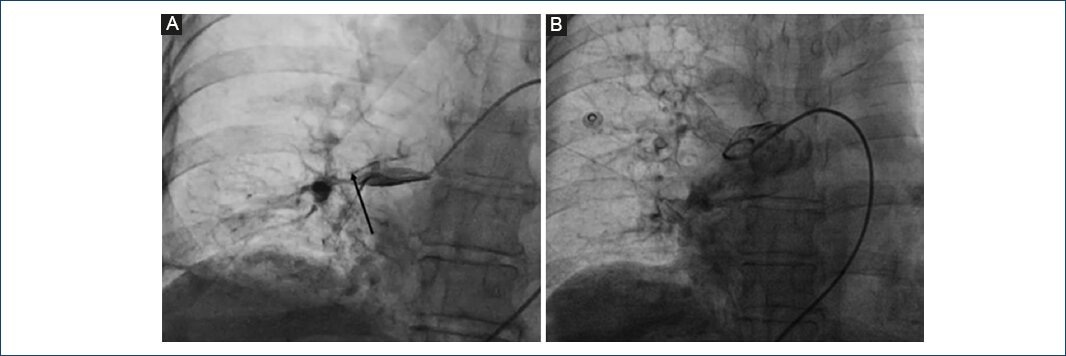

Figura 1 Fase diagnóstica de tromboembolia pulmonar y tratamiento. A: ecocardiograma transtorácico inicial, eje paraesternal largo, en el cual se observa dilatación del VD, proporción VD/VI de 0.98. B: angiotomografía pulmonar en corte axial, con defecto de llenado en la rama derecha de la arteria pulmonar que se extiende a ramas subsegmentarias. C: corte axial a nivel de T5 con mayor definición del defecto de llenado de la rama pulmonar derecha. D: resultado fluoroscópico final con sonda EKOS (BTG-IM, Bothell, Washington), colocada desde el segmento distal de la arteria lobar inferior derecha hasta la bifurcación del tronco pulmonar.

Se inició anticoagulación con heparina no fraccionada (bolo intravenoso 80 UI/kg y después infusión continua hasta alcanzar de forma rápida y mantenida la prolongación del tiempo de activación parcial de tromboplastina [aPTT] entre 1.5 y 2.5 veces el control), y debido a la existencia de contraindicaciones relativas de trombólisis se decide no realizarla. Con el objetivo de evaluar el TDC se realizó cateterismo cardíaco derecho de urgencia, con angiografía pulmonar y toma de las presiones de las cavidades derechas, y se encontró: PSAP 90 mmHg, presión media de la arteria pulmonar (PMAP) 50 mmHg, con flujo lento e imagen nebulosa en la rama principal derecha, con ausencia de flujo distal en la rama pulmonar inferior derecha (Fig. 2 A), válvula pulmonar sin gradiente al trazo de retiro hacia el tracto de salida del VD.

Figura 2 Angiografía pulmonar previa y posterior al tratamiento. A: en proyección anteroposterior, se observa una imagen nebulosa (flecha) en la rama principal derecha con ausencia de flujo distal en ambas ramas subsegmentarias. B: angiografía pulmonar posterior al procedimiento, que muestra mejoría del flujo distal en las ramas subsegmentarias y desaparición de la imagen sugestiva de trombo en la rama principal derecha.

Debido al alto riesgo de sangrado, se decidió iniciar una infusión continua de alteplasa a 1 mg/h durante 12 h. Posterior al retiro de la sonda EKOS con evidente mejoría hemodinámica. Ecocardiográficamente: VD con función sistólica conservada, TAPSE de 19, onda S de 10 cm/s, fracción de acortamiento del 45%; válvula tricúspide con déficit de coaptación que genera jet concéntrico de insuficiencia moderada, PSAP de 50 mmHg, proporción VD/VI de 0.78. A las 48 horas después del TDC se realizó angiografía de control y toma de presiones, y se encontró PSAP 48 mmHg, PMAP 30 mmHg, y con flujo distal normal en la rama derecha de la arteria pulmonar, sin imagen sugestiva de trombo (Fig. 2 B).